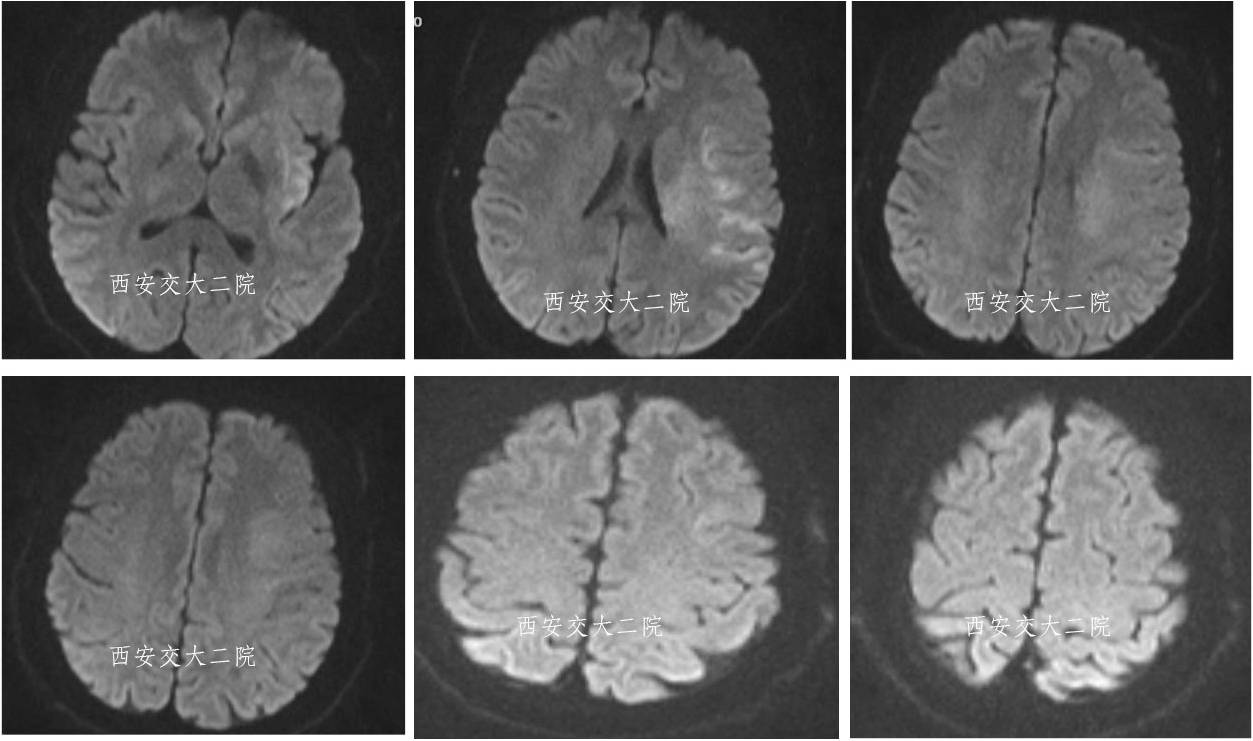

脑MR提示脑干大面积梗死

术后10天MR

术后10天MRA